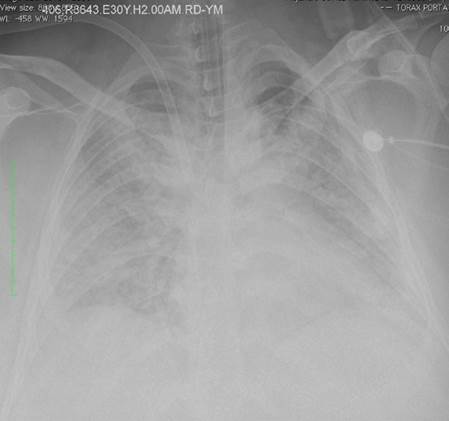

All patients had severe ARDS, according to the Berlin ARDS definition3, and were cannulated for VV ECMO if they had a persistent partial pressure of oxygen/ fraction of inspired oxygen (PaFi) < 100 with a fraction of inspired oxygen > 90% despite optimal medical treatment for 6 hours or less. Patients from other institutions were transferred using air or ground transportation. Figure 1 shows a chest X-Ray in a patient with ARDS.